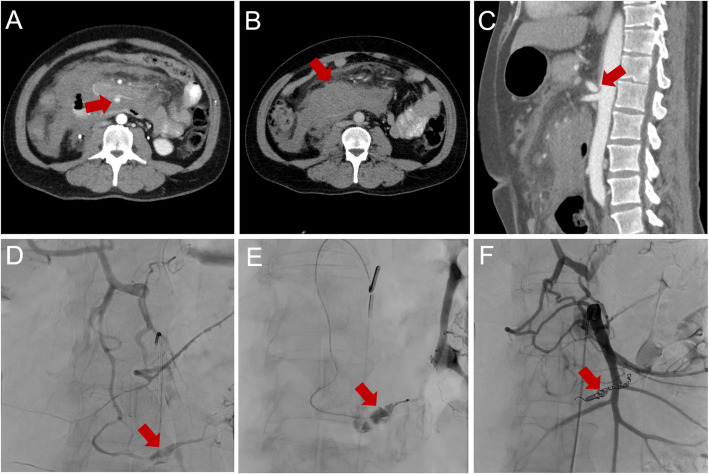

目的:确定胰腺周围动脉瘤(PPAs)中内脏动脉(VA)狭窄的频率和相关性,并为PPAs合并VA狭窄的情况制定统一、更详细的治疗策略,因为目前的指南没有充分解决这一问题。材料和方法:回顾性分析在三级医院诊断的PPAs患者。多发PPAs时,腹腔-肠系膜侧支循环内动脉瘤与血管比值(AVR)最高的动脉瘤为原发性动脉瘤,并根据器官缺血的危险性将其分为“危重”或“非危重”。腹腔动脉和肠系膜上动脉狭窄分级为低(50%)或完全闭塞。治疗策略基于VA狭窄的严重程度、动脉瘤的分类和形态。治疗策略包括血管内、手术和观察等待管理。结果:纳入PPAs患者31例,动脉瘤53个;平均动脉瘤大小:12.5±7.9 mm(范围5-38 mm), AVR: 3.5±2.1(范围1-11.3)。以胰十二指肠上、下动脉及拱廊为主(67.9%)。动脉瘤破裂组AVR明显高于动脉瘤破裂组(6.2±2.8;p = 0.031)。腹腔动脉狭窄占87.1%。动脉瘤大小与活动性出血的发生无相关性(p = 0.925)。11名患者出现了严重的动脉瘤,10名患者需要单独治疗。非危重性动脉瘤多数采用线圈栓塞治疗。结论:CA狭窄、动脉瘤位置和AVR显著影响治疗决策。PPA治疗需要基于解剖学和血流动力学因素的个体化方法。

Results: Thirty-one patients with PPAs were included with a total of 53 aneurysms; mean aneurysm size: 12.5 ± 7.9 mm (range 5-38 mm), AVR: 3.5 ± 2.1 (range 1-11.3). The superior and inferior pancreaticoduodenal arteries as well as the pancreaticoduodenal arcade were affected in most cases (67.9%). AVR was significantly higher in cases of aneurysm rupture (6.2 ± 2.8; p = 0.031). Celiac artery stenosis was present in 87.1%. Aneurysm size and occurrence of active bleeding did not correlate (p = 0.925). 11 patients presented with critical aneurysms, with 10 patients requiring individually tailored treatment. Non-critical aneurysms were treated with coil embolization in most cases.